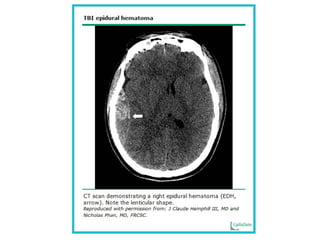

Hemorragia epidural aguda

 Arteria meníngea media

 Respiraciones profundas y luego superficiales

 Pulso lento

 Incremento concomitante de la presión

arterial sistólica (efecto cushing)

 La pupila puede dilatarse en el lado del

hematoma